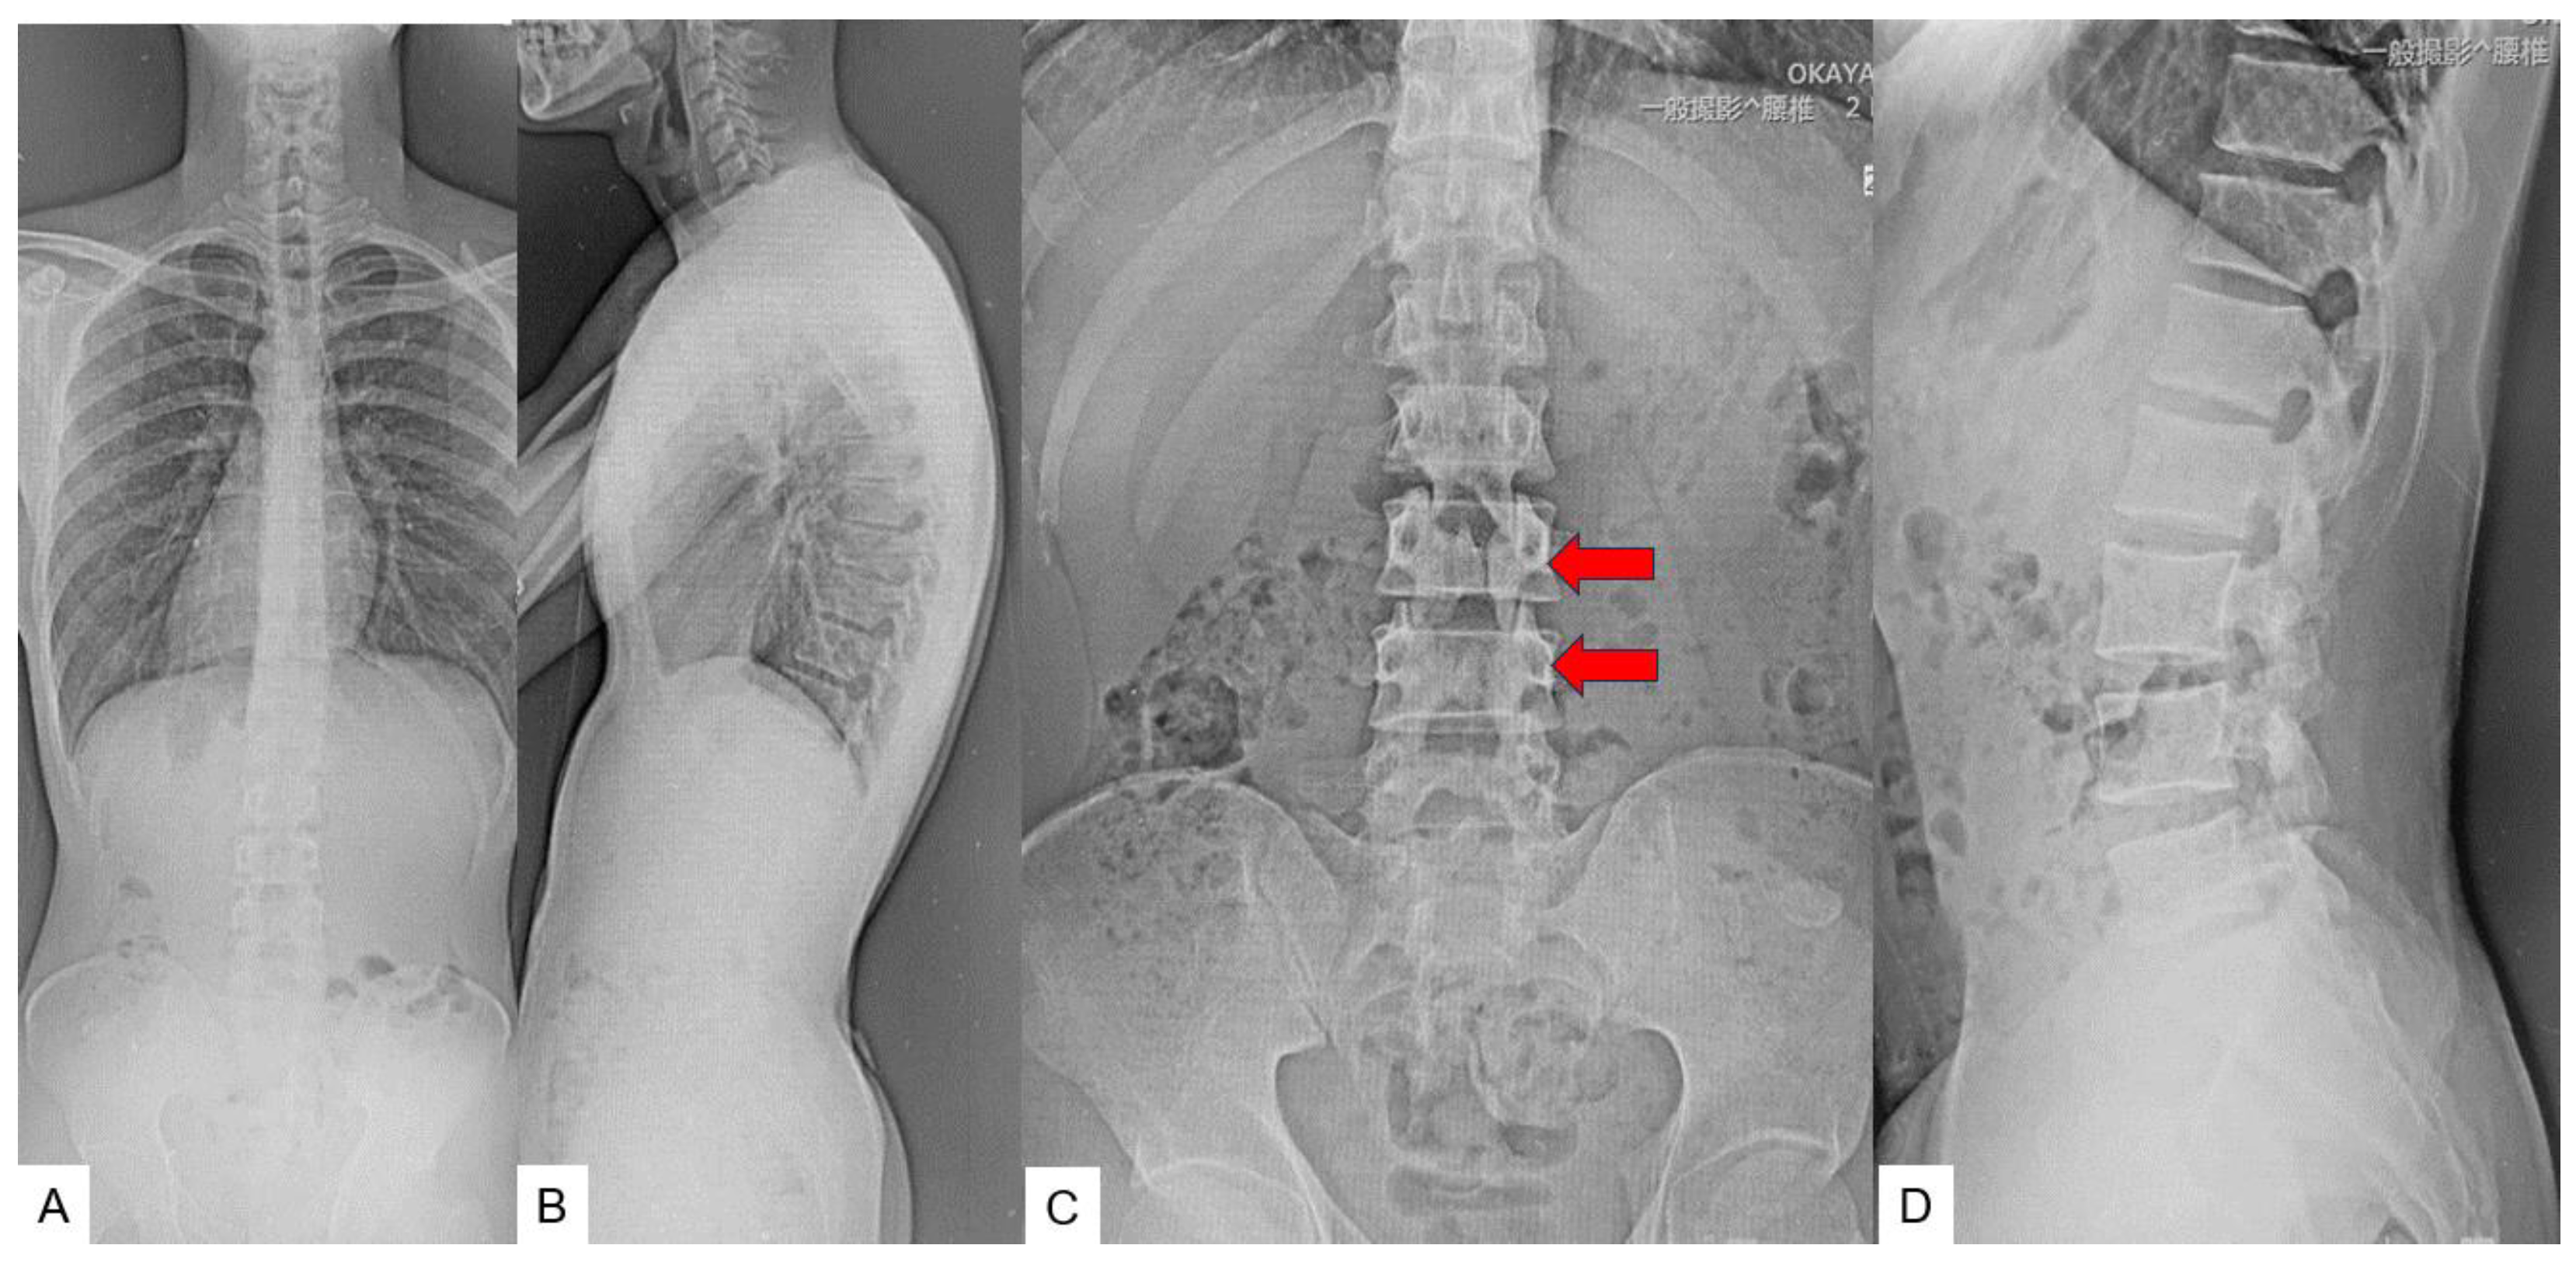

2. Case 1 31 years old male, tethered cord syndrome

2.3. Preoperative imaging